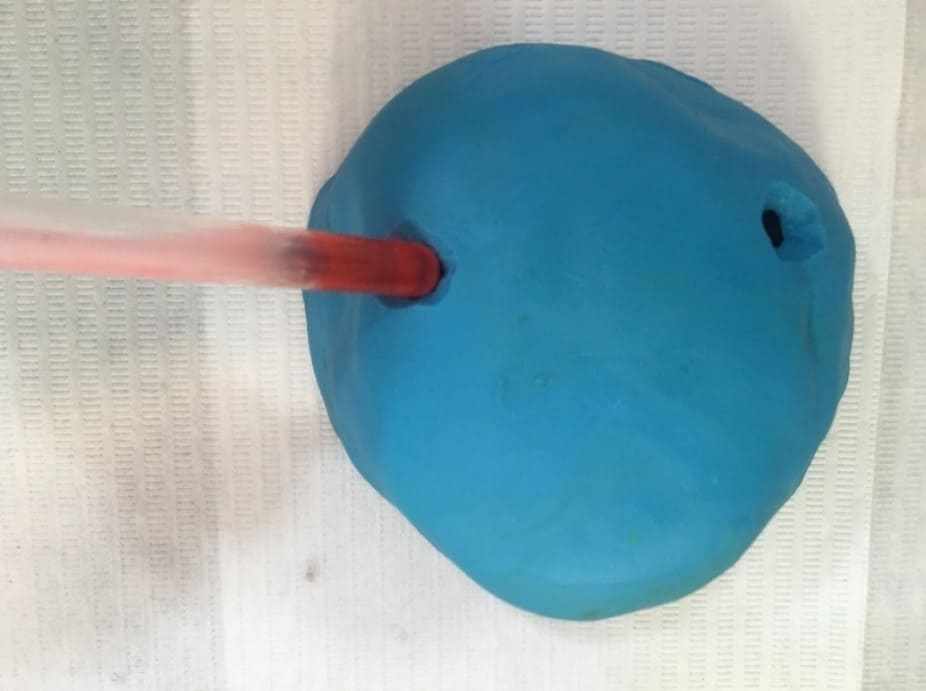

Thus, a new planning for rehabilitation was executed, having as a starting point the facial molding. The clinical sequence used was: skin cleansing by removing makeup and oiliness, protection of hair with bandage, application of solid vaseline in the facial hairs, tamponade of the nostols with cotton wool and a canudo for mouth breathing (figure 25). Then, the alginate (Jeltrate Dustless®, Dentsply, Argentina) was started using two parts, with the proportion of water/powder being 4:4. After being manipulated, it was deposited in small parts in the region to be molded with the aid of a spatula (figure 26), then the retention with cotton on the alginate was performed and the common plaster type II (Asfer®, Brazil) was added, in order to confer stiffness (figure 27), preventing deformation during its removal.

Figure 25: Preparation for the beginning of facial molding.

Figure 26: Alginate deposition on the face.

Figure 27: Insertion of plaster on the retention.

The mold was removed with slight movements, prompting the patient to move the mime muscles (figure 28). Immediately after molding, the mold was filled with type IV plaster (Durone®, Dentsply, Argentina) to obtain the facial model. With the aid of a vibrator, the plaster was deposited on the mold to prevent the formation of bubbles and when taking prey, the model was removed, so the finishes were executed (figure 29). Subsequent surgical removals, the treatment plan of choice was radiotherapy, being performed for two months, where it has already begun and is under medical follow-up.